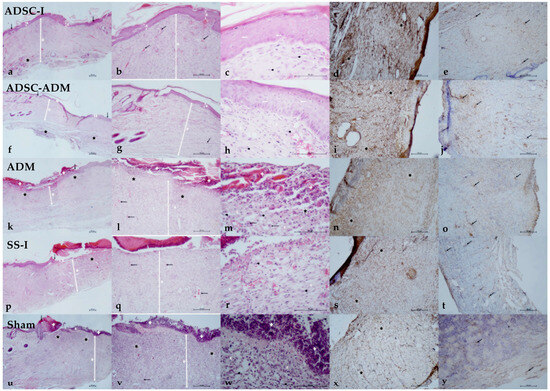

Histopathological evaluation showed significant differences among the groups across multiple healing parameters (Table 2). Inflammatory cell infiltration followed a distinct pattern: while the ADSC-I and ADSC-ADM groups demonstrated intermediate levels and did not differ significantly from one another. The highest inflammation scores occurred in the SS-I, ADM and Sham groups, which were statistically comparable (Table 2, Figure 3).

Figure 3.

Histological outcomes of the treatment strategies. ADSC-I group (a) Excision margins (black arrow), epidermis (E), dermis (D), inflammatory cell infiltration (asterisk). H&E, ×4. (b) Epidermis (E), dermis (D), vessel (arrow). H&E, ×10. (c) Keratinocyte (arrow), fibroblast (arrowhead), connective tissue collagen (C). H&E, ×40. (d) Anti-rpS6 immunoreactivity in the dermal layer (asterisk). IHC, ×10. (e) Anti-TERT immunoreactivity in the dermal layer (arrow). IHC, ×10. ADSC–ADM group (f) Excision margins (black arrow), epidermis (E), dermis (D), inflammatory cell infiltration (asterisk). H&E, ×4. (g) Epidermis (E), dermis (D), vessel (arrow). H&E, ×10. (h) Keratinocyte (arrow), fibroblast (arrowhead), connective tissue collagen (C). H&E, ×40. (i) Anti-rpS6 immunoreactivity in the dermal layer (asterisk). IHC, ×10. (j) Anti-TERT immunoreactivity in the dermal layer (arrow). IHC, ×10. ADM group (k) Excision margin (black arrow, left), necrotic/granulation tissue (+), dermis (D), inflammatory cell infiltration (asterisk). H&E, ×4. (l) Necrotic/granulation tissue (+), dermis (D), inflammatory cell infiltration (asterisk), vessel (arrow). H&E, ×10. (m) Necrotic/granulation tissue (+), keratinocyte (arrow), macrophage (arrow), fibroblast (arrowhead), inflammatory cell infiltration (asterisk), connective tissue collagen (C). H&E, ×40. (n) Anti-rpS6 immunoreactivity in the dermal layer (asterisk). IHC, ×10. (o) Anti-TERT immunoreactivity in the dermal layer (arrow). IHC, ×10. SS-I (Subdermal saline injection) group (p) Excision margin (black arrow, right), necrotic/granulation tissue (+), epidermis (E), dermis (D), inflammatory cell infiltration (asterisk). H&E, ×4. (q) Necrotic/granulation tissue (+), dermis (D), vessel (arrow). H&E, ×10. (r) Fibroblast (arrowhead), connective tissue collagen (C). H&E, ×40. (s) Anti-rpS6 immunoreactivity in the dermal layer (asterisk). IHC, ×10. (t) Anti-TERT immunoreactivity in the dermal layer (arrow). IHC, ×10. Sham group (u) Excision margin (black arrow, right), necrotic/granulation tissue (+), degenerated epidermis (E), dermis (D), inflammatory cell infiltration (asterisk). H&E, ×4. (v) Necrotic/granulation tissue (+), diffuse inflammatory cell infiltration in the dermal layer (asterisk), dermis (D), vessel (arrow). H&E, ×10. (w) Necrotic/granulation tissue (+), fibroblast (arrowhead), connective tissue collagen (C). H&E, ×40. (x) Anti-rpS6 immunoreactivity in the dermal layer (asterisk). IHC, ×10. (y) Anti-TERT immunoreactivity in the dermal layer (arrow). IHC, ×10.

Neovascularization was most pronounced in the groups receiving stem cell–based treatments. The highest degree of new vessel formation occurred in the ADSC-I group, followed by the ADSC-ADM group. In contrast, the Sham, ADM and SS-I groups exhibited similarly low levels of neovascularization, with no significant differences among them (Table 2, Figure 3).

Telomerase (TERT) expression displayed a similar hierarchical distribution. The ADSC-I and ADSC-ADM groups showed the highest expression levels and were statistically comparable. Intermediate expression was observed in the ADM and SS-I groups, whereas the Sham Group consistently exhibited the lowest TERT levels (Table 2, Figure 3).

The expression of ribosomal protein S6 (rpS6), an important marker of wound healing, also differed significantly. The ADSC-I and ADSC-ADM groups demonstrated the highest rpS6 expression levels, which did not differ significantly from each other. The ADM and SS-I groups displayed intermediate levels, while the Sham Group again showed the lowest expression (Table 2, Figure 3).